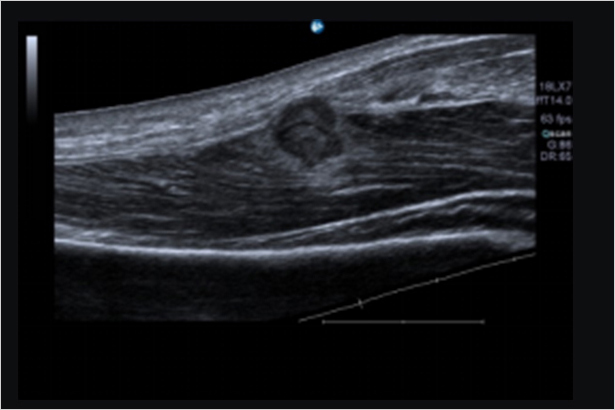

可連續獲取超聲圖像,擴展視野,采集大面積的診斷信息